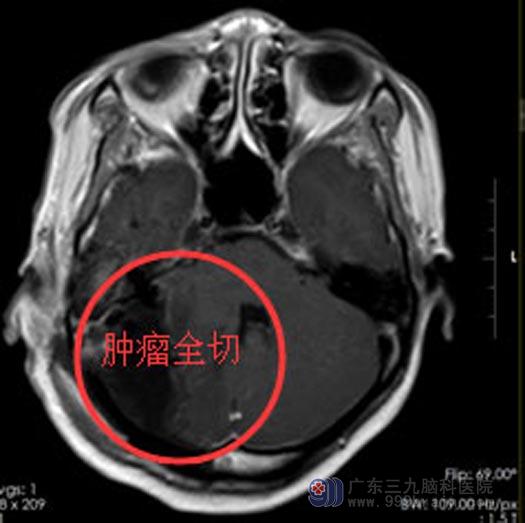

充分的检查与术前准备后,由综合神经外科鲁明副院长主刀在全麻下行“右侧桥小脑角占位切除术”。由于肿瘤体积巨大,手术难度极大,经过显微镜下几个小时的细心操作,肿瘤被完整切除。

患者术后安返病房,术后第一天情况平稳,头痛头晕症状消失,术后一周满意出院。